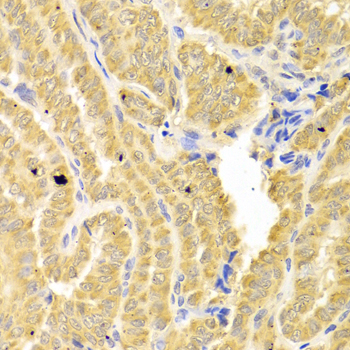

Immunohistochemistry of paraffin-embedded human endometrial cancer using IL1R2 antibody at dilution of 1:100 (x400 lens).